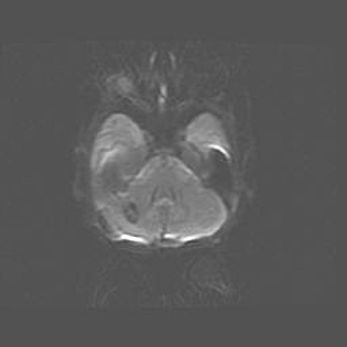

Подострая гематома правой гемисферы мозжечка.

Наружная гидроцефалия.

Возраст: 15 дней

Вес: 3100 г

Пол: женский

Окружность головы: 37 см

Срок гестации: 35-36 недель

При открытой наружной форме гидроцефалии у новорожденных расширяются и переполняются субарахноидные пространства.

Кровоизлияния в мозжечок имеют две клинико-анатомические формы: полушарные гематомы и кровоизлияния в червь.

К появлению этой патологии может привести: повреждения головного мозга, возникающие в результате асфиксии и гипоксии плода при беременности, или травмы во время родов. Редко гематома мозжечка может быть результатом первичной коагулопатии и сосудистой мальформации, диссеминированном внутрисосудистом свертывании, изоиммунной тромбоцитопении.